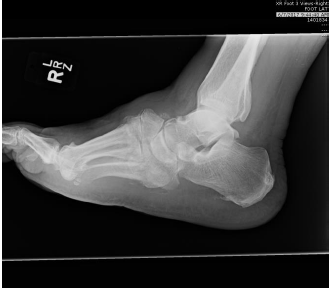

The patient was a 52-year-old man with Charcot neuroarthropathy who underwent medial and later column beaming, joint arthrodesis of the second and third tarsometatarsal joints with nitinol staples, and Achilles tendon lengthening. The patient subsequently developed wounds on the dorsal and medial aspects of the foot, which resisted local wound care therapies and debridement, notes the poster.

A patch test revealed an allergic reaction to titanium. The authors note that after radiographic union occurred, all implants were removed, and the wound resolved a month later. The authors urge a higher level of suspicion for hypersensitivity reactions.